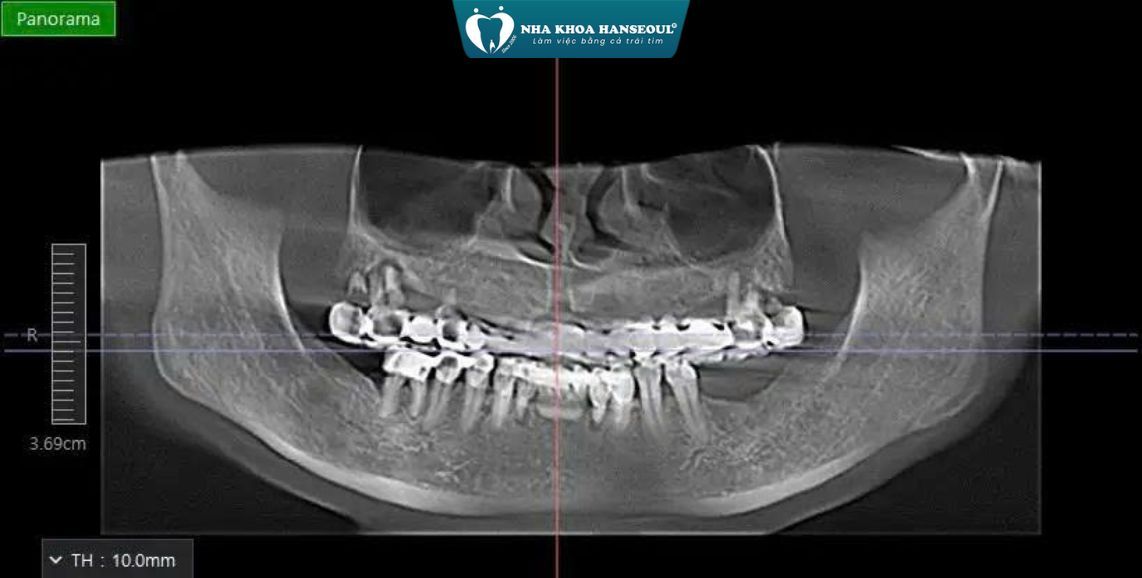

1 Tình trạng ban đầu

Qua thăm khám lâm sàng và chụp CT ConeBeam 3D, bác sĩ ghi nhận:

- Mất răng vùng hàm dưới: R36 – R37 – R47

- Tình trạng tiêu xương tại các vị trí mất răng do để trống lâu ngày